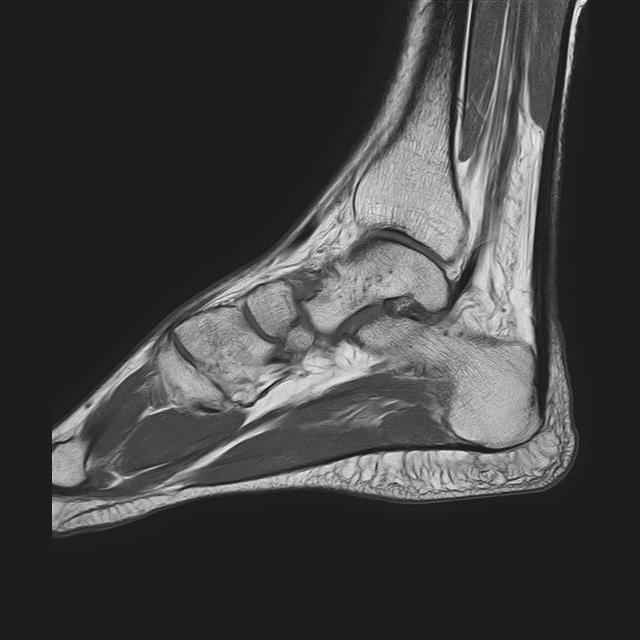

Дорогие коллеги,Мужчина 36 лет, пострадал около 8 месяцев назад в ДТП (водитель мотоцикла).

Подтаранный вывих лечили гипсовой лонгетой. Недиагностированным остался перелом ладьевидной кости, который беспокоит в настоящее время. Аваскулярный некроз кости, похоже. Добавил наиболее значимые снимки, на мой взгляд.

По данным снимкам однозначно сказать о некрозе ладьевидной кости нельзя. Типичные изменения при аваскулярном некрозе ладьевидной кости, как правило, начинаются в центральной её части с дальнейшим развитием коллапса. В данном случае в значительной степени пострадал таранно-ладьевидный сустав, вероятнее всего, именно это является причиной болевого синдрома. При отсутствии эффекта от физиотерапии и ношения ортопедической обуви в течение ближайших 6 месяцев придётся ставить вопрос о таранно-ладьевидном артродезе.